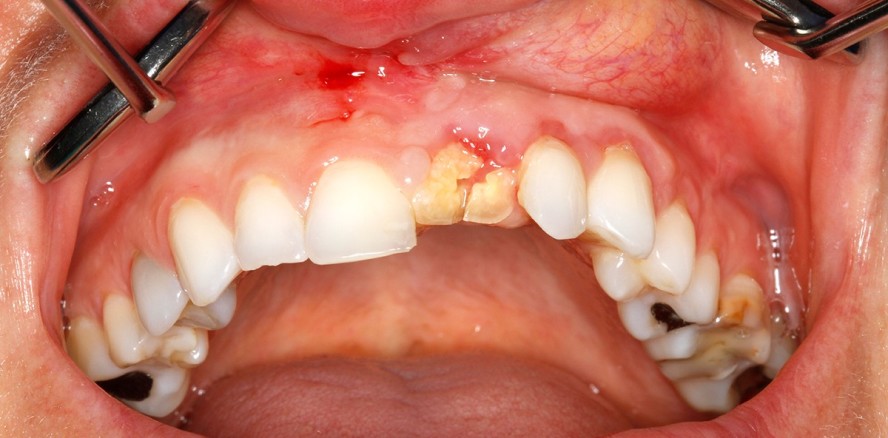

Eine 33-jährige Landwirtin wurde mit den Hinterbeinen eines Pferdes ins Gesicht getreten. Aufgrund multipler Gesichtsverletzungen und einer drohenden Verlegung der Atemwege wurde sie nach Eintreffen der Rettungskräfte schutzintubiert und in die Universitätsklinik Hamburg-Eppendorf eingeliefert. Ein CT zeigte neben einer Schädel­basisfraktur mit Einbeziehung des Felsenbeins und knöcherner Einstrahlung in den rechten Karotiskanal, eine komplexe zentrale Mittelgesichtsfraktur mit Beteiligung beider Orbitaböden, des Nasenskeletts, der Sinus maxillae beidseits sowie des Nasenseptums. Darüber hinaus bestand eine Weichteilver­letzung des rechten Nasenrückens, der Oberlippe sowie eine Trümmerfraktur mit Kronen- und Wurzelbeteiligung des Zahnes 21.

Bereits vor Entlassung erfolgte die Vorstellung im medizinischen Versorgungszentrum zur Planung der dentalen Rehabilitation. Aufgrund der isolier­ten Trümmerfraktur des Zahnes 21 war eine Sofortimplantation unter maximaler Gewebeschonung mittels hochpräziser Bien-Air-Technologie das Mittel der Wahl. Im Rahmen der Wundkontrolle einige Tage nach Entlassung erfolgte die Implantatplanung sowie eine Abdrucknahme von Ober- und Unterkiefer zur Erstellung von Situ-Modellen.

Im Folgenden wurde der Zahn 21 in Lokalanästhesie extrahiert und mittels Titan-Sofortimplantat (BEGO Semados RSX) versorgt. Die genaue Einschub­richtung wurde zuvor ermittelt und eine individuelle Bohrschablone an­gefertigt. Zur Optimierung des ästhe­tischen Ergebnisses wurden leichte Knochendefizite im koronaren Bereich durch Einbringen von Knochenersatzmaterial (BEGO OSS in feiner Körnung) ausgeglichen. Eine Adaptationsnaht mit ETHILON 5-0 stabilisierte das Gewebe um den Gingivaformer. Im Anschluss erfolgte die Lagekontrolle mittels Panoramaschichtaufnahme.